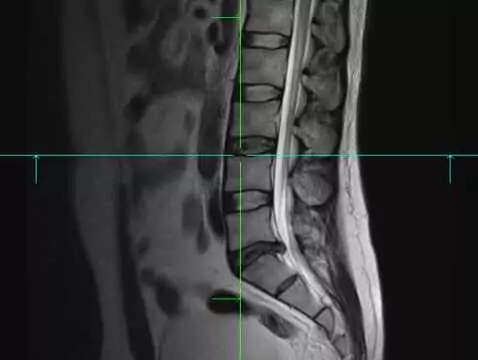

Eine Diskopathie ist nichts anderes als der Vorfall einer Bandscheibe aus ihrem Platz, ihrer natürlichen Position. In den meisten Fällen betrifft die Diskopathie die untere Wirbelsäule (sakrale und...

Eine Diskopathie ist definiert als der Anfangszustand einer degenerativen Erkrankung der Wirbelsäule. Wenn eine Diskopathie unbehandelt bleibt, schreitet sie sehr schnell voran. Diskopathie wird als...

Diskopathie, ist ein sehr weit gefasster Begriff, der verschiedene Arten von Bandscheibenerkrankungen umfasst. Zu den Ursachen der Prozesse, die zur Degeneration der Bandscheibe führen, gehören...